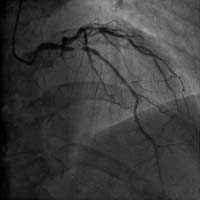

冠心病介入诊疗技术:包括冠状动脉造影术、经皮冠状动脉腔内成形及支架术(PCI)、经桡动脉冠状动脉介入治疗(TRI)、血流储备分数(FFR)测定等。介入团队24小时候命,能胜任急诊PCI。对慢性闭塞性病变(CTO)的治疗亦达到国内先进水平。

介入手术治疗严重冠心病